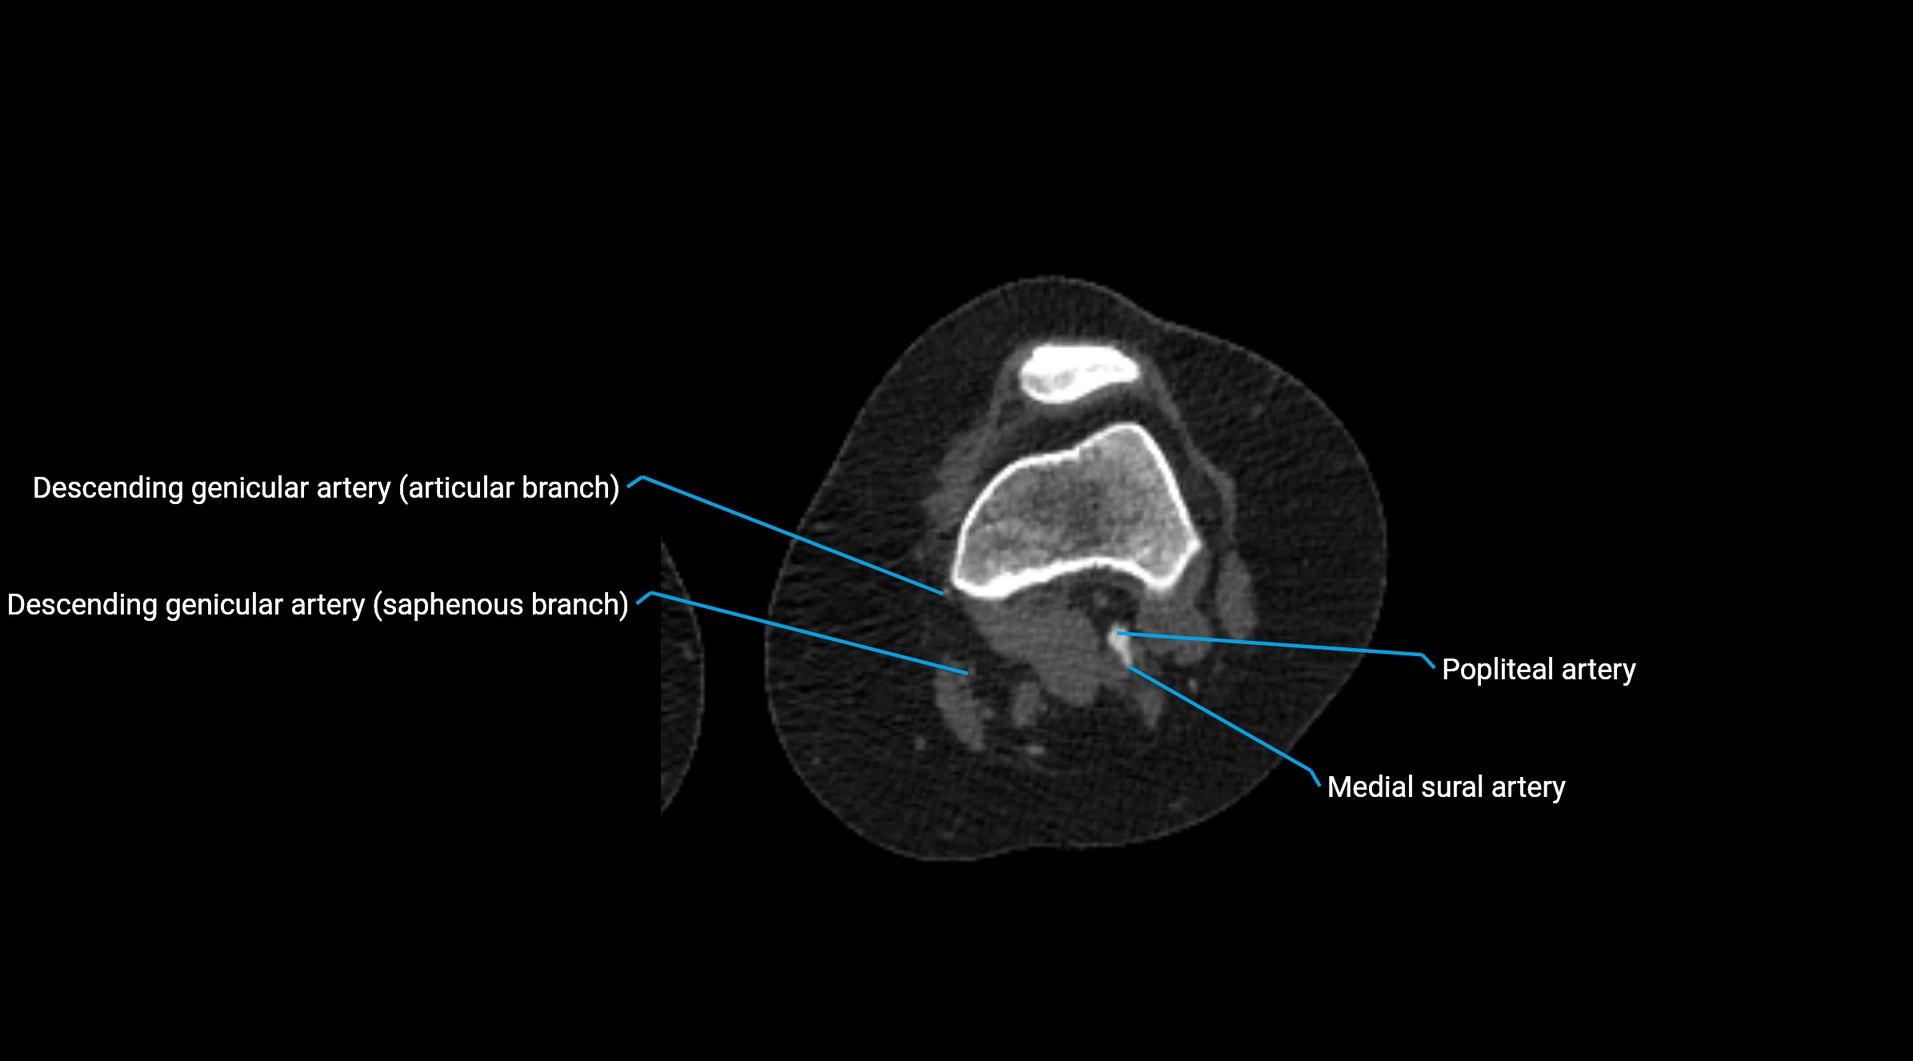

Contrast-enhanced CT (CTA):

• Gold standard for abdominal aortic imaging

• Provides excellent detail of lumen, wall, aneurysm, thrombus, and branch vessels

• Multiplanar and 3D reconstructions help in aneurysm measurement, stent graft planning, and dissection evaluation

• Detects acute rupture, traumatic injury, or occlusion with high sensitivity